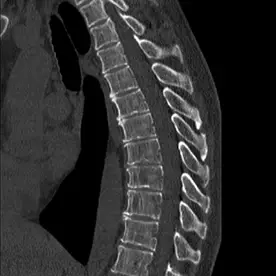

In der sagittalen Rekonstruktion im Knochenfenster (Bild 3) zeigt sich eine Osteopenie mit degenerativen Veränderungen im Altersmaß und teils mehrsklerosierten Irregularitäten der Grund- und Deckplatten der unteren BWS und des thorakolumbalen Übergangs. Kein Nachweis von suspekten osteolytischen oder entzündlichen ossären Prozessen im Rahmen einer ossären Manifestation der Lungentuberkulose.